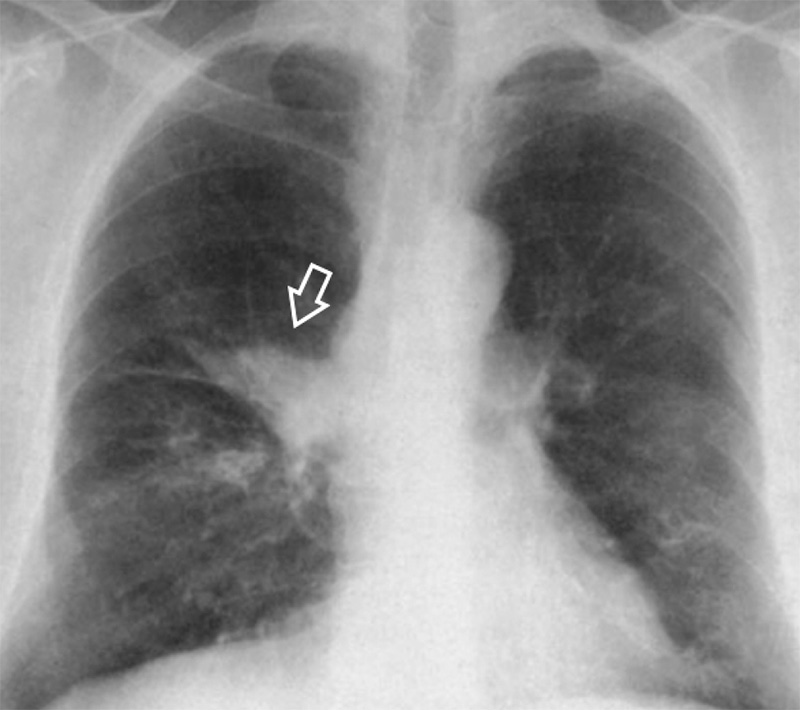

Визуализация и диагностика неинвазивного аспергиллеза с помощью КТ

Раздел: Необычные решения